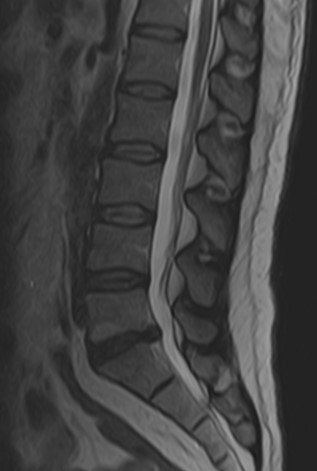

Lomber MRG İncelemesi - L5-S1 Bulging Lomber MRG İncelemesi - Dejeneratif Disk Hastalığı

Resim 1: Lomber MRG incelemesinde L5-S1 seviyesinde santral bir bulging görülmektedir. Sağ S1 köküne dokunacak şekilde anulus fibrozusta küçük bir açıklık ve ufak bir ekstrüde fragman varlığından şüphe edilebilse bile, kesin söylenemez. Aynı seviyede disk içi hipointens ve komşu L5 vertebrası alt endplate'i ön kısmında dejeneratif sinyal değişikliği görülmektedir (dejeneratif disk hastalığı). Lomber lordoz korunmuştur. Diğer disk seviyeleri, faset eklemler ve paravertebral kaslarda belirgin bir sorun saptanmamıştır.